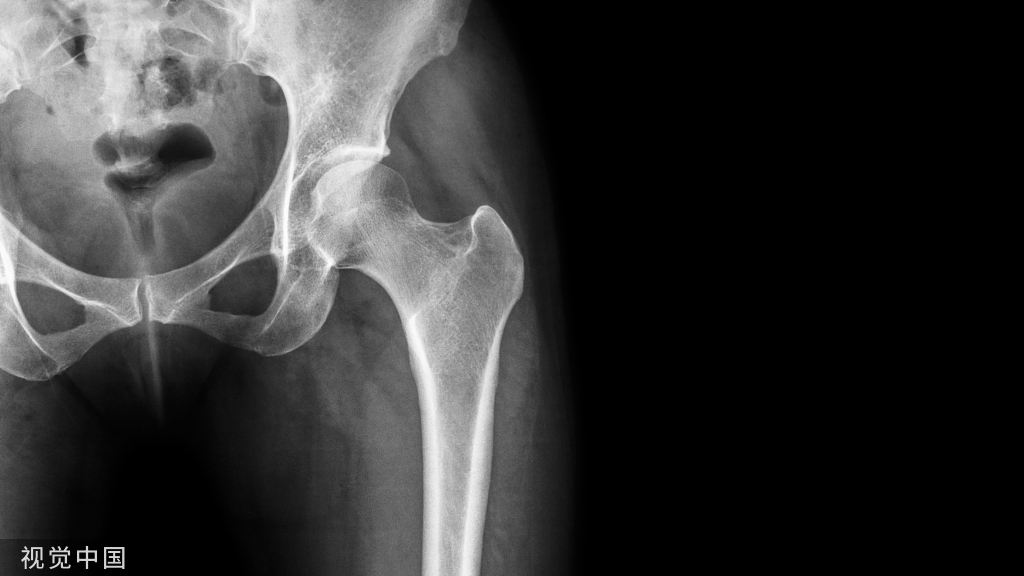

术前准备X线检查,确认骨折愈合

内固定物的识别,厂家,型号,接口,相应的器械手术入路,是否设计神经血管等问题。断裂的内固定,需要更加充分的准备!